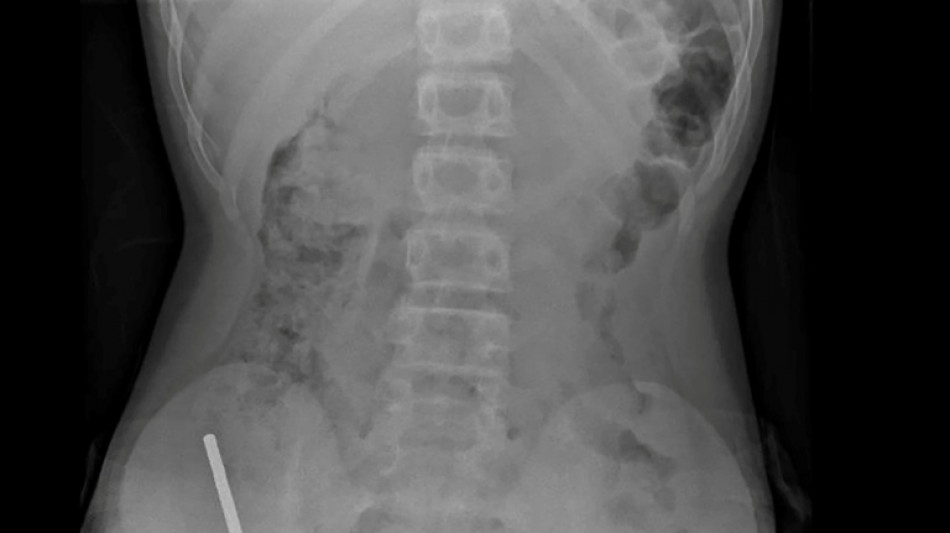

Nouvelle-Zélande: un adolescent opéré après avoir ingéré près de 100 aimants achetés sur Temu / Photo: Handout - NEW ZEALAND MEDICAL JOURNAL (NZMDJ)/AFP

"Il avoué avoir ingéré entre 80 et 100 aimants puissants au néodyme, de 5x2mm environ, une semaine plus tôt", indique un rapport des médecins de l'hôpital de cet hôpital, publié dans le New Zealand Medical Journal (NZMJ).

Les médecins ont déclaré que la pression exercée par les aimants avait provoqué une nécrose dans quatre zones de l'intestin grêle et du gros intestin du garçon.

Il a été opéré afin que l'on lui retire les aimants et les tissus nécrosés, et il a pu rentrer chez lui après huit jours à l'hôpital.